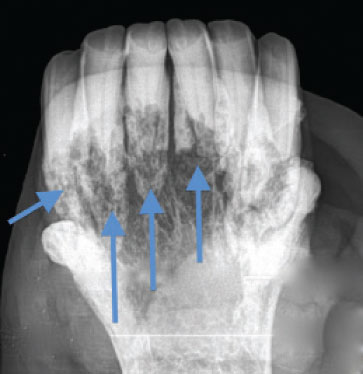

![]() Blue arrows show extensive resorption affecting the roots of these lower incisors in a horse with advanced EOTRH |